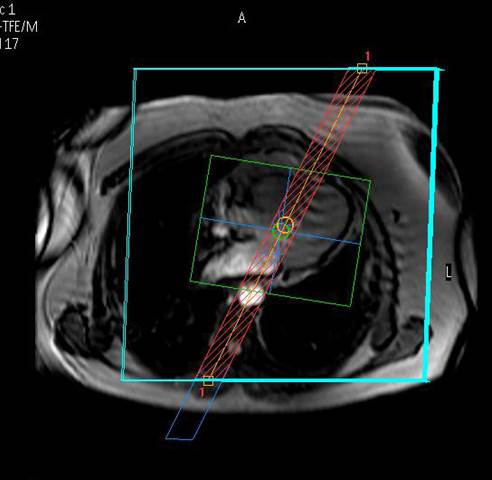

spielt seit der Erstinstallation eines MR-Tomographen im Jahr 1996 eine weltweit führende Rolle bei der klinischen Anwendung, Forschung und Ausbildung auf dem Gebiet der CMR. Wir untersuchen mit zwei MRT-Systemen

modernster Bauart pro Jahr ca. 3000 Patienten, wobei das gesamte diagnostische Spektrum abgedeckt wird.

Wir bieten modernste MRT-Diagnostik.

Ganzkörper MR System - Philips healthcare